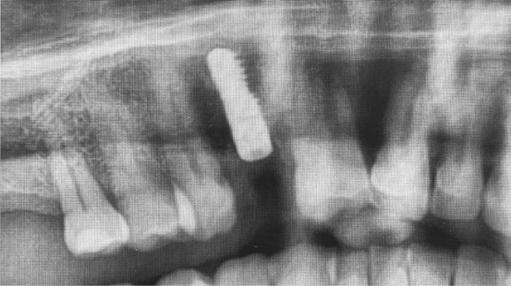

Fundamental surgical skills — hard tissue augmentation (Figure 2)

Figure 1: Suggested hard tissue progression – Increasing degree of difficulty of hard tissue augmentation

Figure 2: Fundamental skills for hard tissue augmentation

Figures 3A-3D: dPTFE ridge preservation technique. 3A. Immediate post-op. 3B. 4 weeks post-op. 3C. Membrane removal, note dense CT. 3D. 6 week post-op. 3E. 4-month post-op. 3F. Versah® osseodensification with buccal roll flap. 3G. Tapered, platform switched, 16 deg. conical connection implant placed with 45 Ncm insertion torque. Custom healing abutment